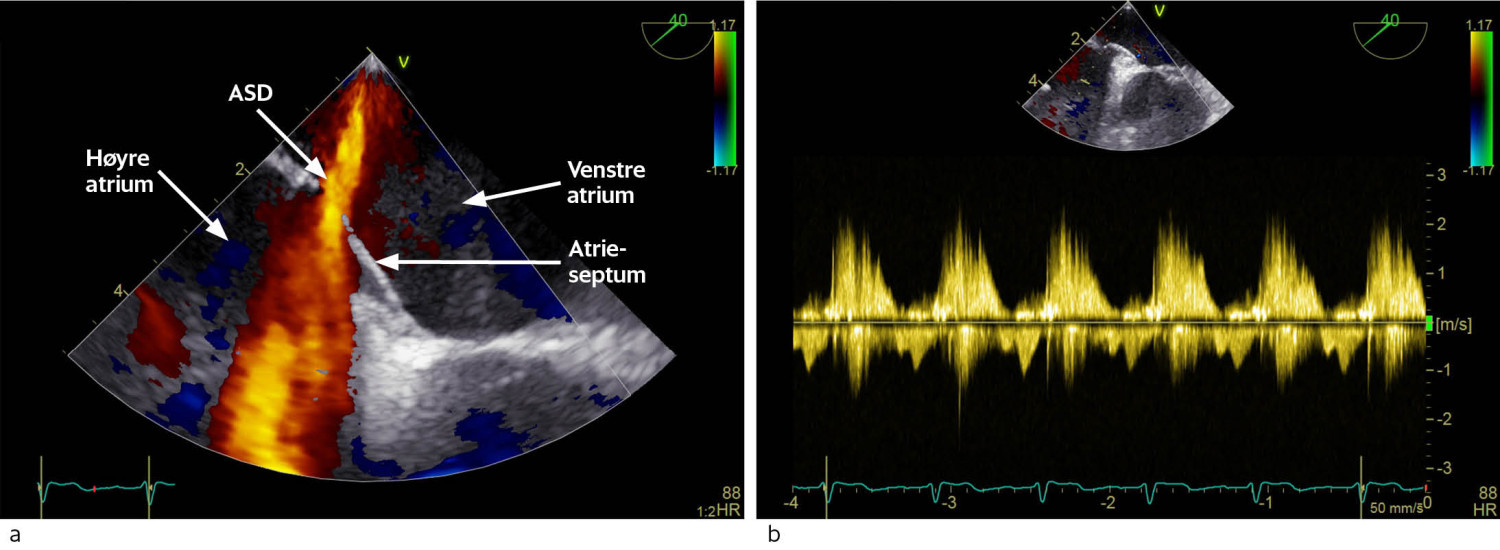

Operasjonen ble utført som en standard åpen hjerteoperasjon med median sternotomi og bruk av hjerte-lunge-maskin. Man anla først venebypass til circumflexarterien. Atrieseptumdefekten ble identifisert og lukket med direkte sutur. Inspeksjon av trikuspidalklaffen avdekket chordarupturer til anteriore seil, som var patologisk fortykket. Det ble gjort forsøk på klaffereparasjon, men dette ga ikke patent klaff. Det ble derfor innsatt en biologisk klaff i trikuspidalposisjon til godt ekkokardiografisk resultat (figur 3). Pasienten var sirkulatorisk og respiratorisk stabil og ble ekstubert ukomplisert seks timer etter kirurgislutt. Transtorakal ekkokardiografi to dager postoperativt viste god høyre ventrikkelfunksjon, velfungerende trikuspidalventil og ingen holdepunkter for restlekkasje over atrieseptum. Venstre ventrikkel-funksjon var fortsatt normal, med ejeksjonsfraksjon 60 %.